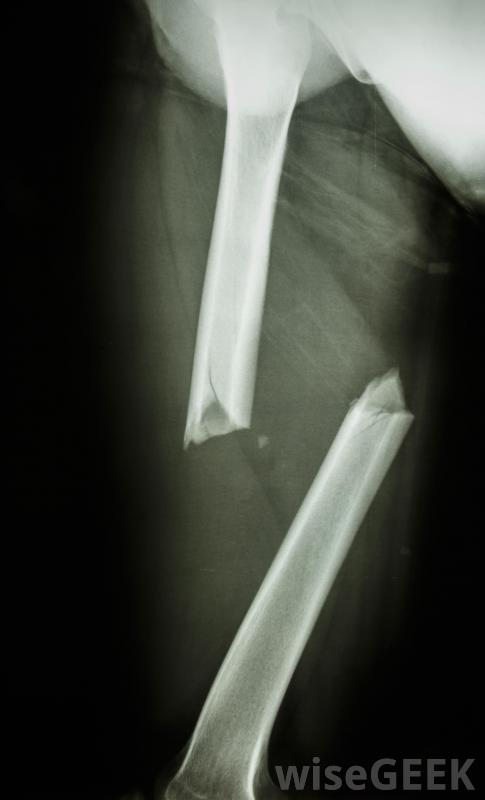

骨骼中的生长板是骨骼结构中最薄弱的部分IV型骨折贯穿骨骺、骺板和干骺端。对于这种非常严重的损伤,通常需要进行手术,以使骨块完全对齐。如果在手术过程中不能保持良好的对齐恢复期,骨正常生长的前景不佳。

骨骺骨折常见于胫骨下端骨骺板压缩性骨折是罕见的,通常包括骨头末端和生长板的压碎,这种损伤属于V型骨骺骨折,预后差,最典型的是导致生长发育不全,很难被发现,而且通常在正常生长障碍变得明显之前仍然无法被诊断出来。这类骨折通常需要外科治疗,而且通常还需要后期的矫正手术

儿童的骨骼可能会出现一些医学问题有些分类系统增加了一个Ⅵ型骨骺骨折,其中部分骨骺、骺板和干骺端完全缺失。这类骨折通常是外伤造成的,如重型机械事故、枪伤等。与V型骨折一样,这些骨折通常需要手术治疗和随后的重建手术。它们通常也会导致生长发育迟缓。